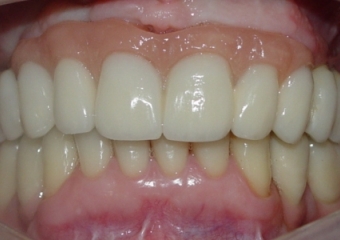

Prótese fixa instalada sobre implantes

Sorriso do caso finalizado em novembro de 2010